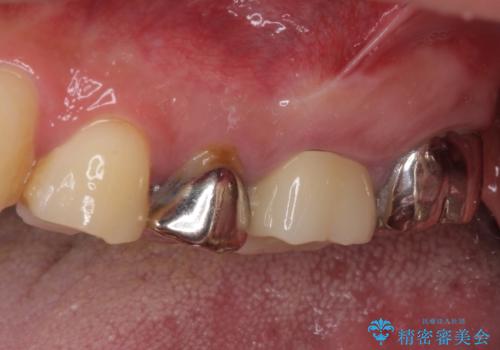

- 奥歯が痛いとのことで来院された患者様です。

歯肉に排膿の痕があり、叩いたり咬んだりすると痛みを感じていました。

根管治療を行い、その後フルジルコニアクラウンにて補綴することとしました。